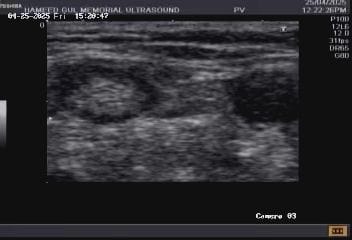

At Hameed Gul Memorial Ultrasound Institute and Clinics, we take pride in offering a comprehensive and continually growing collection of ultrasound images and videos. Our archive spans the full spectrum—from the ultrasound appearance of normal anatomical structures to a wide range of pathological findings, including rare and complex cases seldom encountered in routine practice.

Our institutue provides high-quality ultrasound imagies for various diagnostic applications. these images serve as essential tools for accurate diagnostic and treatment planning.